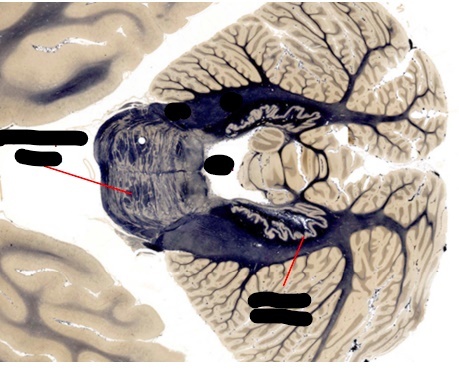

what is the vermis?

discuss the relationship of the vermis with the 4th ventricle?

what portion of the cerebellum contain the deep cerebellar nuclei?

which of these nuclei is normally visible?